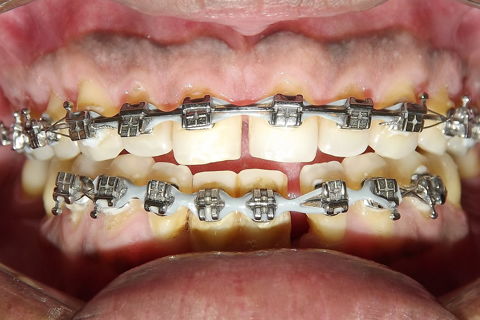

fotos iniciais do caso.

Paciente do sexo masculino, 36 anos, brauifacial. Relatava que os Diastemas lhe incomodavam muito, e em tratamento anterior o profissional fez exo de 2 incisivos centrais inferiores e instalou Prótese movel com 4 incisivos, após um tempo de uso a prótese começou a incomodar. em planejamento com o implantodontista ficou definido o fechamento dos diastemas e reabilitação dos elementos 41 e 31 com implantes.

segue as fotos do caso